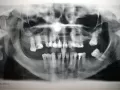

Хотела полечить зубы за рубежом на туристическом отдыхе в Европе, но возникли некоторые сомнения в компетентности европейского доктора. Был сделан панорамный снимок, и за 30 минут осмотра врач несколько раз поменял свое мнение от "зубы в ужасном состоянии, под корнями гной" до абсолютно противоположного. Конечно, я знаю, что зубы в сложном состоянии, но хотелось бы Вас спросить, видите ли Вы какой-то гной на снимке в деснах под корнями?

Есть ли возможность поставить мостик на зубы со стороны L, или попробовать вставить штифты в корни и сделать коронки? Или по данному снимку уже единственная возможность съемные протезы? Буду благодарна за объективную оценку ситуации, насколько это конечно возможно на расстоянии.

Я постараюсь дать вам полную консультацию по вашим зубам.

Начнем с сегмента L: 35 и разделенные уже корни 37 необходимо удалить, однозначно и даже думать нечего и через три месяца можно устанавливать имплантаты, как минимум 4 шт, на 38 на верхушке есть воспаление, диагноз периодонтит, необходимо пролечить.

Теперь сегмент R: также 46 зубе периодонтит.

На верхней челюсти так же перегрузка на 1.3, 1.7 зубе, слишком продолжительный мостовидный протез, недопустимый пролет для моста, а справа консольная конструкция, что так же является недопустимой.

В общем то все, проблем много, если вы в Москве, приезжайте мы составим вам правильный план лечения с успешным результатом!